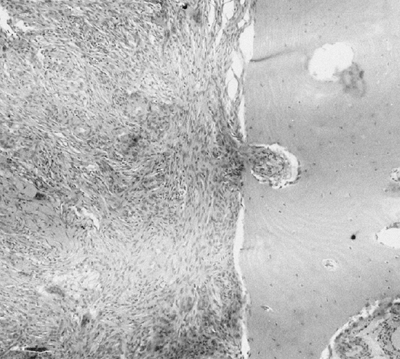

seen (Fig. 14.9).

![]() |

Figure 14.9 A:

Typical histologic appearance of an osteoblastic osteosarcoma. There is immature bone being formed from cells that vary in size, shape, and amount of nuclear material. These findings are typical of malignant cells (10 × magnification) B: Higher magnification (40 ×) of the osteosarcoma in (A). The nuclear detail is more clearly seen, and the bone seemingly coming directly from these bizarre cells makes the diagnosis of an osteosarcoma. |